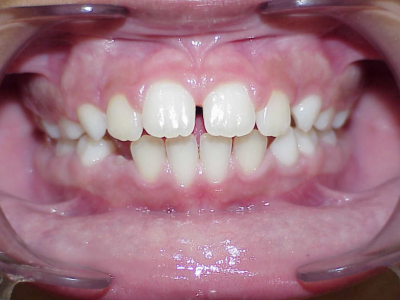

Behandeling Hajar

eindfoto

Beschrijving

Leeftijd bij aanvang: 9 jaar

1-6 maanden Bonded Hyrax in de bovenkaak, banden/slotjes in de onderkaak met Transforce

7-13 maanden: Twinblock

14-47 maanden: Volledig banden/slotjes in de boven-en onderkaak (omdat er hier blijvende kiezen ontbraken moesten er kiezen getrokken worden en de ontstane ruimtes gesloten, dit verklaart de langere behandeltijd)

Retentie fase: Wrap en C-CBar